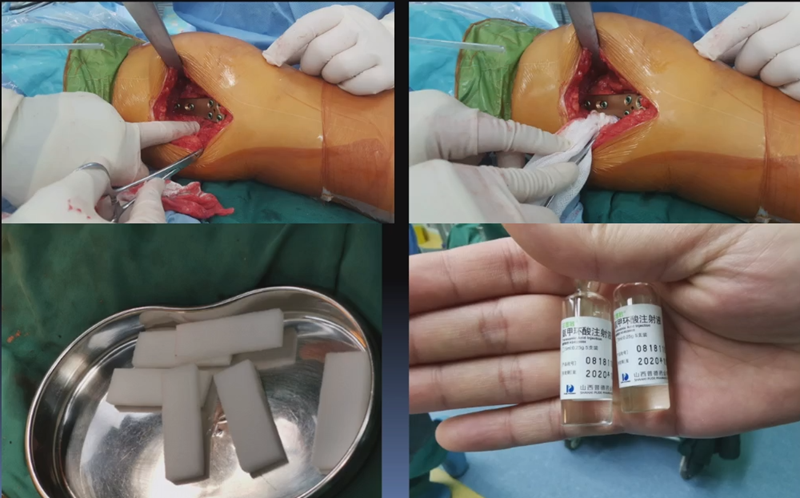

术中发现螺钉松动,截骨端出现坎插迹象。

近端螺钉松开,调整力线,重新固定后,在外侧加小钢板抗旋。

术后10周复查,力线较好。